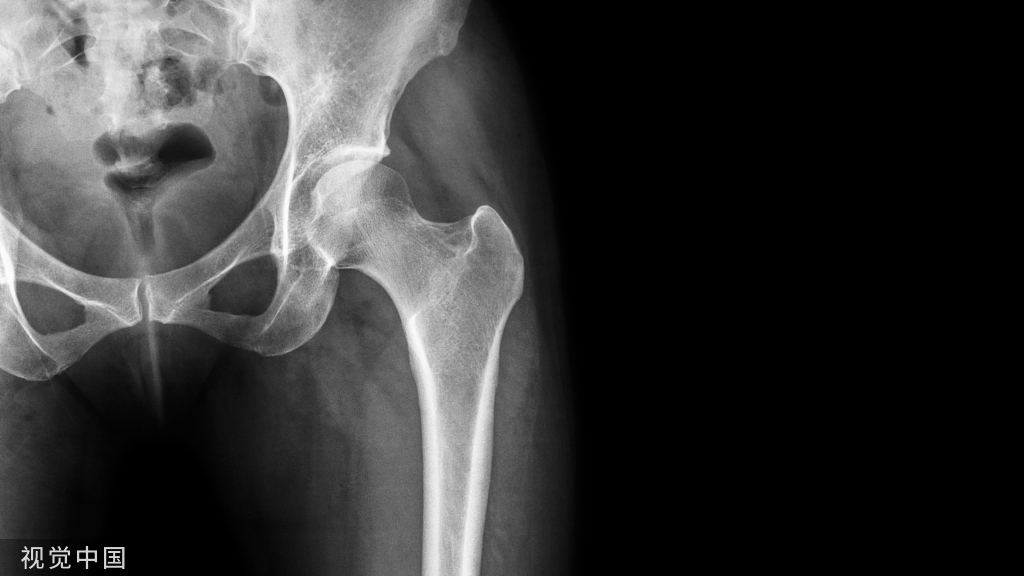

股骨转子间骨折内固定选择:

Evans 分型

I型为顺转子间型(分四个亚型)。

‖型为反转子间型,由于内收肌的作用,骨折远端向内侧移位。

Evans分型定义了稳定骨折与不稳定骨折。